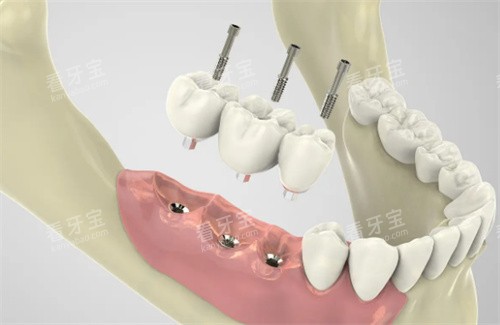

在种植牙领域,大岭山地区各牙科机构都配备了较高的技术和设备。牙博士口腔采用智能化精细种植技术,通过可靠的智能化技术,可以精细地进行种植手术,确保种植结果的质量和稳定性。医院为每一位患者量身定制更合适的种植方案,实现口腔美学与功能的理想结合。

天使口腔在疑难种植牙方面有丰富经验,能够处理复杂的种植病例。医院配备的较高设备和技术团队,确保种植手术的靠谱性和成功概率。

价格参考:进口种植牙6800-16000元起/颗,韩国登腾种植牙5002元起,美国皓圣种植牙8002元起,瑞典诺贝尔种植牙11802元起,瑞士ITI种植牙12002元起。

从价格体系来看,大岭山地区的牙科收费相对合理。种植牙方面,韩国登腾种植牙5002元起,美国皓圣种植牙8002元起,瑞典诺贝尔种植牙11802元起,瑞士ITI种植牙12002元起,基本与市场均价持平。

1.种植牙需求:如果需要进行种植牙手术,建议选择牙博士口腔或天使口腔,这两家机构在种植牙方面有丰富的经验和较高的技术设备。